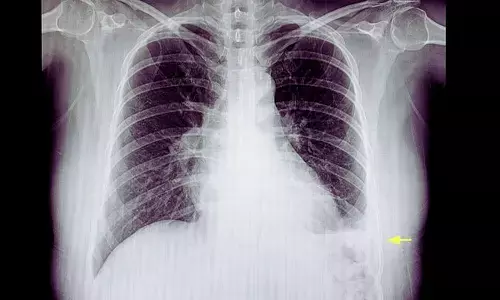

Intrapleural Enzyme Therapy Outperforms Saline Lavage in Pleural Infection: SCOPE Trial

Spain: A study published in the European Respiratory Journal reports that saline lavage alone may prolong pleural drainage in patients with pleural Infection compared with intrapleural enzyme therapy (IET). The findings also indicate that adding saline lavage to IET does not provide a meaningful clinical advantage over enzyme therapy alone.

- Early radiographic improvement was similar across all treatment groups.

- By day 2, all groups showed a median reduction of about 30% in pleural effusion size.

- By day 5, patients receiving enzyme therapy demonstrated greater pleural fluid resolution, with a median residual effusion of zero.